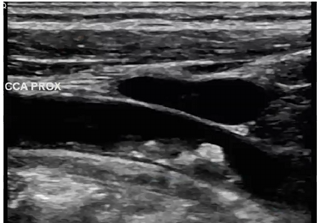

In this image, what structure is anterior to proximal CCA

portion of the IJV